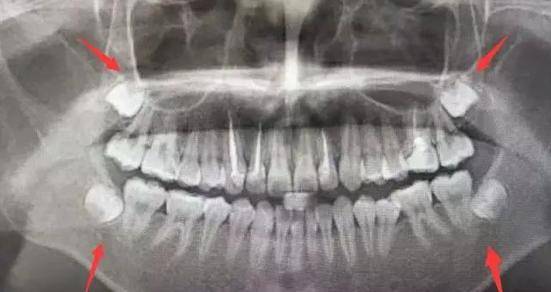

最佳答案: 智齿,俗称智慧齿,立事牙,尽头牙,是口腔最靠近喉咙的牙齿,如果全部生长出来一共4颗,上下颚各两颗,一般是于16岁或之后才生长出来。相较于幼儿时期长出的乳齿与

最佳答案: 你好,根据你的情况,智齿一般是在17到20岁间萌出,如果萌出位置较正,则会顺利萌出,对于咀嚼功能也会有一定帮助,如果萌出位置,方向,高度上发生异常,比如智齿倾

智齿什么时候长 您的浏览器不支持播放视频,请升级。 视频内容 首先说一下什么是智齿,智齿从口腔里边一般情况下是人类的第3颗磨牙,第3颗磨牙是从前往后数第8颗牙齿,也叫